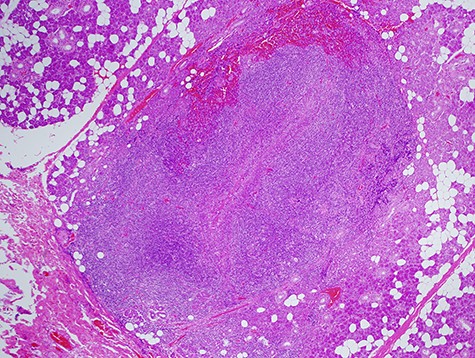

In the histological report, only fibrous scar was found without a sign of fistula or epithelial cells (Fig. 4).

Histological specimen showing the string-like structure. No epithelial cells were observed by the pathologists.

Histologically (Fig. 10), fibrosis and inflammatory granulation were seen. Inflammatory reaction of lymph nodes was observed. Epithelial cells could not be found in the slices.

Histological specimen of the final surgery. Inflammatory reaction of a lymph node inside of parotid the parotid gland was observed.

Histologically, no epithelial cells nor lumen was identified inside of it. The epithelial structure was presumed to have been small and escaped from the slices for histology.